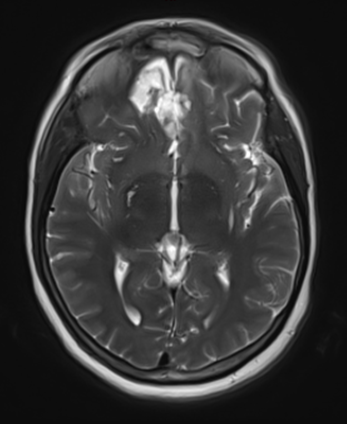

Figure 2a – Preoperative MRI demonstrating an extra-axial lesion with surrounding vasogenic edema and mass effect on the frontal lobes.